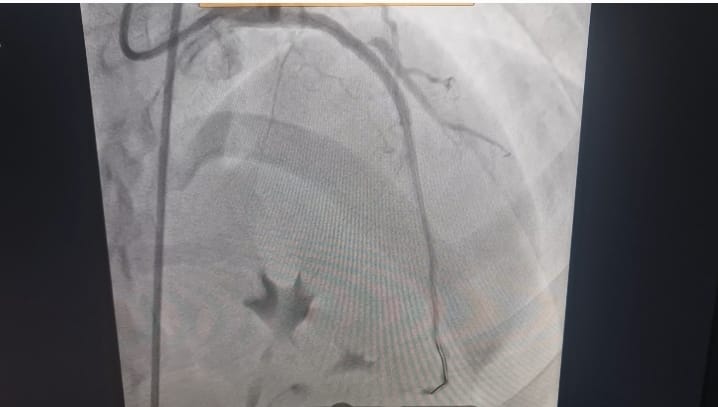

وعلى الفور، قرر الفريق الطبي إجراء قسطرة قلبية عاجلة، حيث تم اكتشاف انسداد تام بالشريان الأمامي، وتم فتحه وتركيب دعامة بنجاح كامل، مما أدى إلى استقرار حالة الشاب وإنقاذ حياته في اللحظات الحرجة.